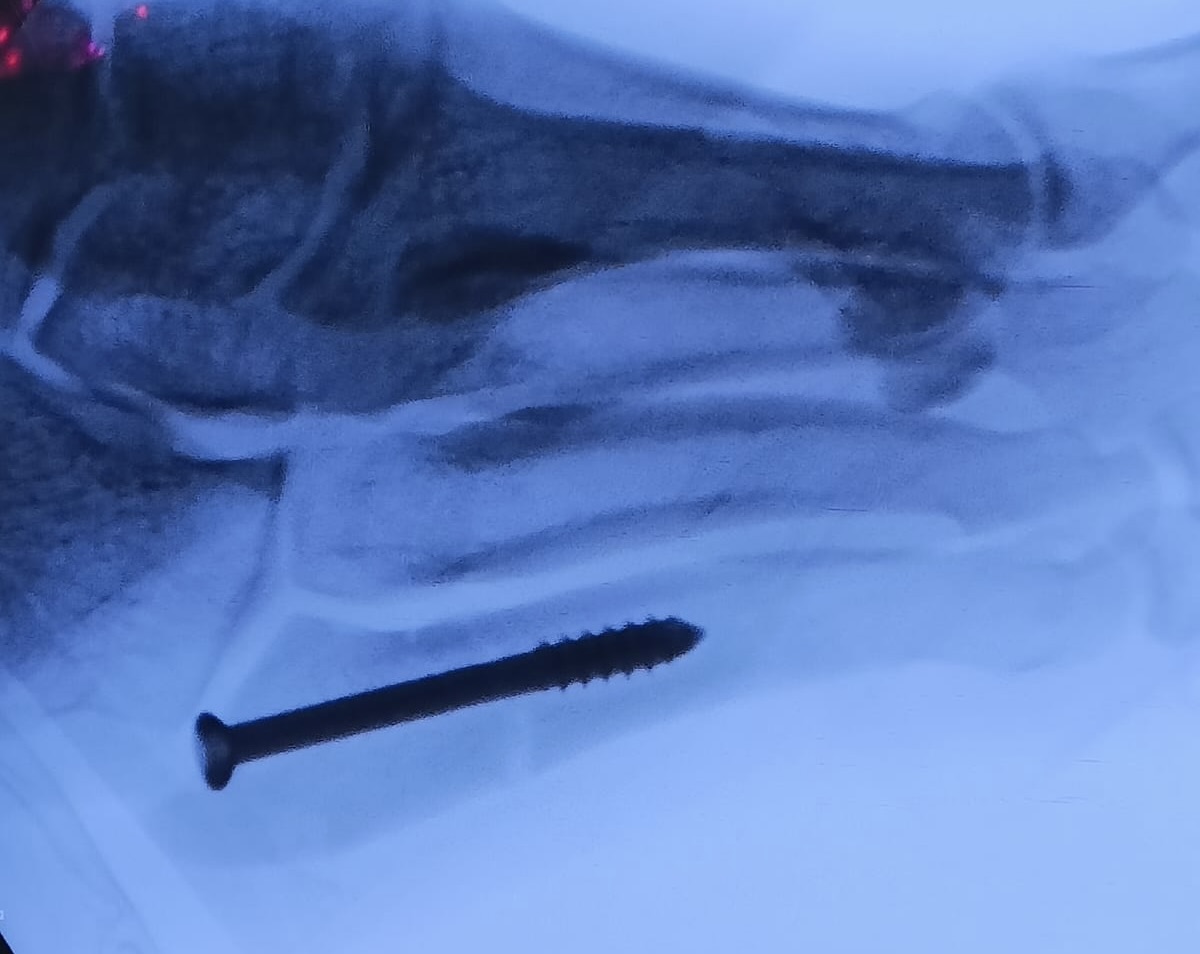

Fracturas del quinto metatarsiano(Fractura de Jones)

Las fracturas del quinto metatarsiano son lesiones muy típicas en el deporte. En muchos casos se trata de fracturas por sobrecarga o estrés.

Son lesiones que generalmente se tratan de manera conservadora con una inmovilización durante 6 semanas aproximadamente, aunque en caso de deportistas, personas con alta demanda funcional o re-fracturas se puede optar por tratamiento quirúrgico mediante osteosíntesis, generalmente un tornillo intramedular.